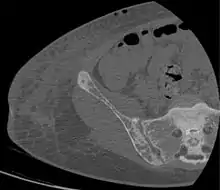

CT shows focal areas of osteosclerosis.[18] Brown tumors in the pelvis and a hip fracture.[18]

Brown tumors in the pelvis and a hip fracture.[18] Subchondral resorption in the sacroiliac joint.[18]